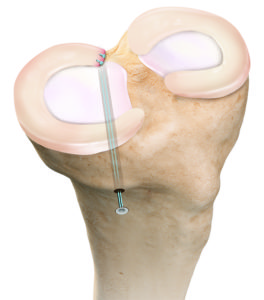

Die Befestigung des in den meisten Fällen abgerissenen Hinterhornes des Meniskus führen wir minimalinvasiv mittels Gelenkspiegelung durch. Hierbei wird die abgerissene Wurzel mit einer speziellen Nahttechnik und einem sehr stabilen Fadenmaterial armiert. Anschliessend wird der Bereich, in dem der Meniskus ausgerissen ist, angefrischt. Mit einem kleinen Bohrer wird nun durch den Unterschenkel ein Kanal gebohrt, durch welchen dann die an der Wurzel befestigten Fäden nach vorne ausgeleitet werden. Hier erfolgt dann unter Zug die Befestigung des Meniskus, exakt an der Stelle des Ausrisses, indem die Fäden vorne am Knochen befestigt werden. Dies kann mit einem kleinen Metallplättchen zusätzlich verstärkt werden.

Nachbehandlung

Bis der Meniskus wieder angeheilt ist vergehen 6 Wochen. In dieser Zeit muss eine Teilbelastung an Stöcken durchgeführt werden. Auch wird die Beugung in dieser Zeit durch eine Schiene limitiert. Schuheinlagen, welche zu einer reduzierten Belastung des Gelenkanteils führen in welchem der Meniskus wieder befestigt wurde kommen nach der Operation ebenfalls zum Einsatz. In wenigen Fällen muss das evtl eingebrachte Metallplättchen wieder entfernt werden.